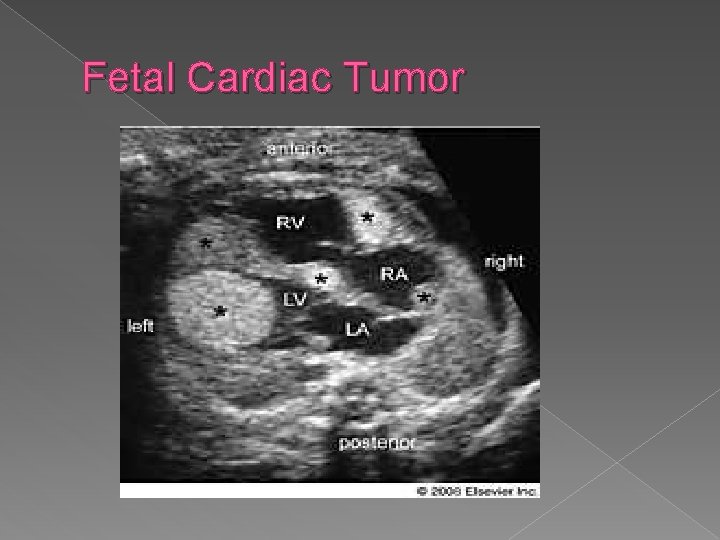

Cardiac Tumors � Cardiac tumors are rare, and include rhabdomyomas, cardiac fibromas, myxomas and teratomas. 30 -78% of patients with cardiac rhabdomyomas have tuberous sclerosis. Prognosis depends on the size, number and location of the tumor(s), as well as associated arrhythmias and anomalies. �

Fetal Cardiac Tumor